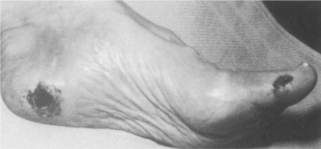

ULCERATION.: Sensory neuropathy, occurring as a result of improper glucose metabolism and diminished vascular perfusion to nerve tissues, places the diabetic person at risk for the development of ulcers. Diabetic foot ulcers are caused primarily by repetitive stress on the insensitive skin with increased pressure and/or horizontal (shear) stress. Body weight and activity level increase the force that the foot must transmit, and this also may increase pressure and shear force, especially in the presence of an underlying bony prominence or foot imbalance. In addition, previously healed ulcers leave scars that transmit force to underlying tissues in a more concentrated manner and hold the fat pad locally so that it cannot function physiologically. As a result, it cannot transmit shear forces, and it becomes damaged easily.

The loss of autonomic nerve function eliminates the production of sweat, leaving the skin dry and inelastic. Changes in pressure and gait, fat atrophy, and muscle weakness are mechanical factors that, along with sensory neuropathy, influence the development of plantar skin abnormalities, especially ulceration.21,229 Diabetes-induced changes in the skin are likely to contribute to ulceration because the collagen and keratin (a protein that is the principal constituent of epidermis, hair, and nails) may be glycosylated (saturated with glucose) with increased cross-linking, which makes the skin stiff. Keratin builds up in response to the increased pressure, covering the openings of unhealed ulcers, and cannot be removed as readily as normal keratin.

The areas most commonly affected by foot ulcers are the plantar areas of the metatarsal heads, the toes, and the plantar area of the hallux (Fig. 11-13). In the Charcot foot, the incidence of ulceration beneath the talus and navicular bones becomes more common because of the rigid rocker-bottom deformity.